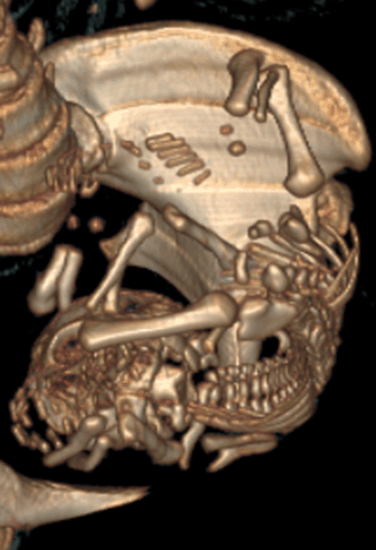

A 20-year-old female G1P0 presented to the obstetric department for the first time, with history of 28 weeks amenorrhea for routine antenatal examination. There was history of third-degree consanguineous marriage. She had her antenatal examination at a peripheral hospital. She was taking iron and folic acid (dosages of iron and folic acid were normal). Ultrasound done at our hospital as a routine, revealed a fetus with occipital meningocele (Figure 1), bilateral enlarged echogenic kidneys (Figure 2), polydactyly, and severe oligohydramnios. We found no liver abnormalities. For the precise analysis of polydactyly, a CT scan of the uterine contents was made. It showed a postaxial polydactyly affecting the four extremities, with six fingers at each hand and six toes at each foot (Figure 3). The scanner also found an occipital bone defect from which the encephalon herniated.

Figure 3: Computed tomography scan intrauterine image with polydactyly (six digits).

Meckel–Gruber syndrome is associated with multiple anomalies. It is characterized by classic triad of polycystic dysplastic kidneys, occipital encephalocele (or other anomalies of the central nervous system) and polydactyly [2]. All these three anomalies (triad) were found in our case. According to Sergi et al. [8], polycystic kidneys were found in all cases (100%), occipital encephalocele in 90% of case and post-axial polydactyly in 83.3% of cases. Salonen et al. [5] found a constant association between cystic dysplasia and liver fibrosis, and concluded that these two abnormalities, together with any other abnormalities of the nervous system, suffice to diagnose MGS. Fraser et al. [9] argue that only cystic renal dysplasia is essential for diagnosis. Wrigth et al. [10] never observed cystic dysplasia. The lack of consensus for the diagnosis of MGS led some authors to conclude that none of the anomalies of the triad or liver fibrosis is essential for diagnosis. The CT scan was almost never used for the diagnosis of MGS in literature. However, it can allow bone analysis in cases where the ultrasound is insufficient and the MRI scan is not available. In our case, the CT scan allowed to diagnose polydactyly and occipital defect.